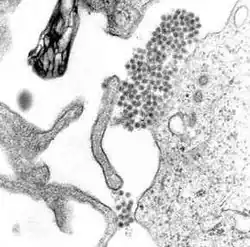

Dengue virus (DENV) is an RNA virus of the family Flaviviridae; genus Flavivirus. Other members of the same genus include yellow fever virus, West Nile virus, and Zika virus. Dengue virus genome (genetic material) contains about 11,000 nucleotide bases, which code for the three structural protein molecules (C, prM and E) that form the virus particle and seven other protein molecules that are required for replication of the virus.[32][33] There are four confirmed strains of the virus, called serotypes, referred to as DENV-1, DENV-2, DENV-3 and DENV-4. The distinctions between the serotypes are based on their antigenicity.[34]